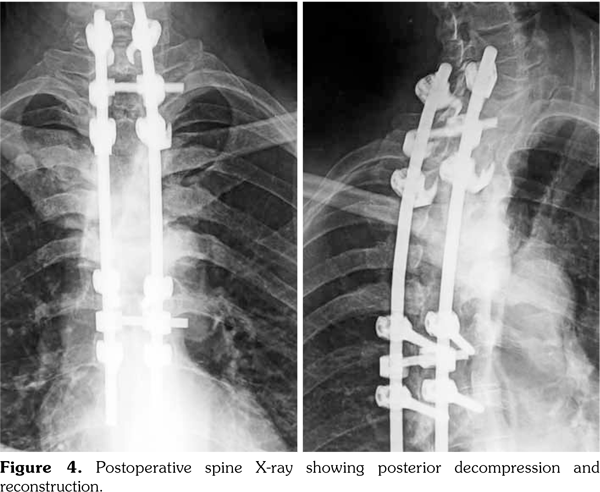

Thus, the diagnosis of SAPHO syndrome was established. Despite the use of nonsteroidal antiinflammatory drug, the disease remained active as attested by Bath Ankylosing Spondylitis Disease Activity Index at 6.7 at three-month follow-up. Then, the patient was lost to follow-up. One year later, he presented with hypesthesia and muscle weakness of his lower limb associated with kyphotic deformity and sphincter symptoms. He was unable to walk. Magnetic resonance imaging showed a vertebral collapse associated with spinal cord compression at T5 (Figure 3). Surgical treatment based on decompression and reconstruction with screw fixation was performed (Figure 4). The histopathology of the specimen obtained surgically showed nonspecific osteomyelitis with an infiltration of inflammatory cells and abnormal fibrous hypertrophy among the trabecular bone. One year later, etanercept was administered at a dose of 50mg weekly, leading to complete resolution of articular manifestations. Clinical remission was obtained under etanercept (Bath Ankylosing Spondylitis Disease Activity Index at 2.1). After two years of follow-up, patient’s paralysis improved by surgery, and he was progressively able to walk.